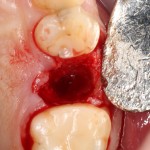

Что мы и сделали. Удалили зуб:

Критически важно провести удаление аккуратно, чтобы не разрушить и без того тонкие стенки альвеолы. Вообще, в хронометраже операции немедленной имплантации удаление зуба занимает 75% времени, это наиболее сложная и деликатная часть вмешательства.